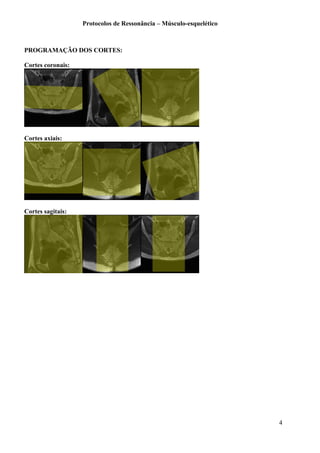

Os cortes coronais devem cobrir da sínfise púbica até os tendões isquitibiais.

Os cortes axiais devem cobrir da crista ilíaca à tuberosidade isquiática.

PROGRAMAÇÃO DOS CORTES:

Cortes coronais:

Cortes axiais: